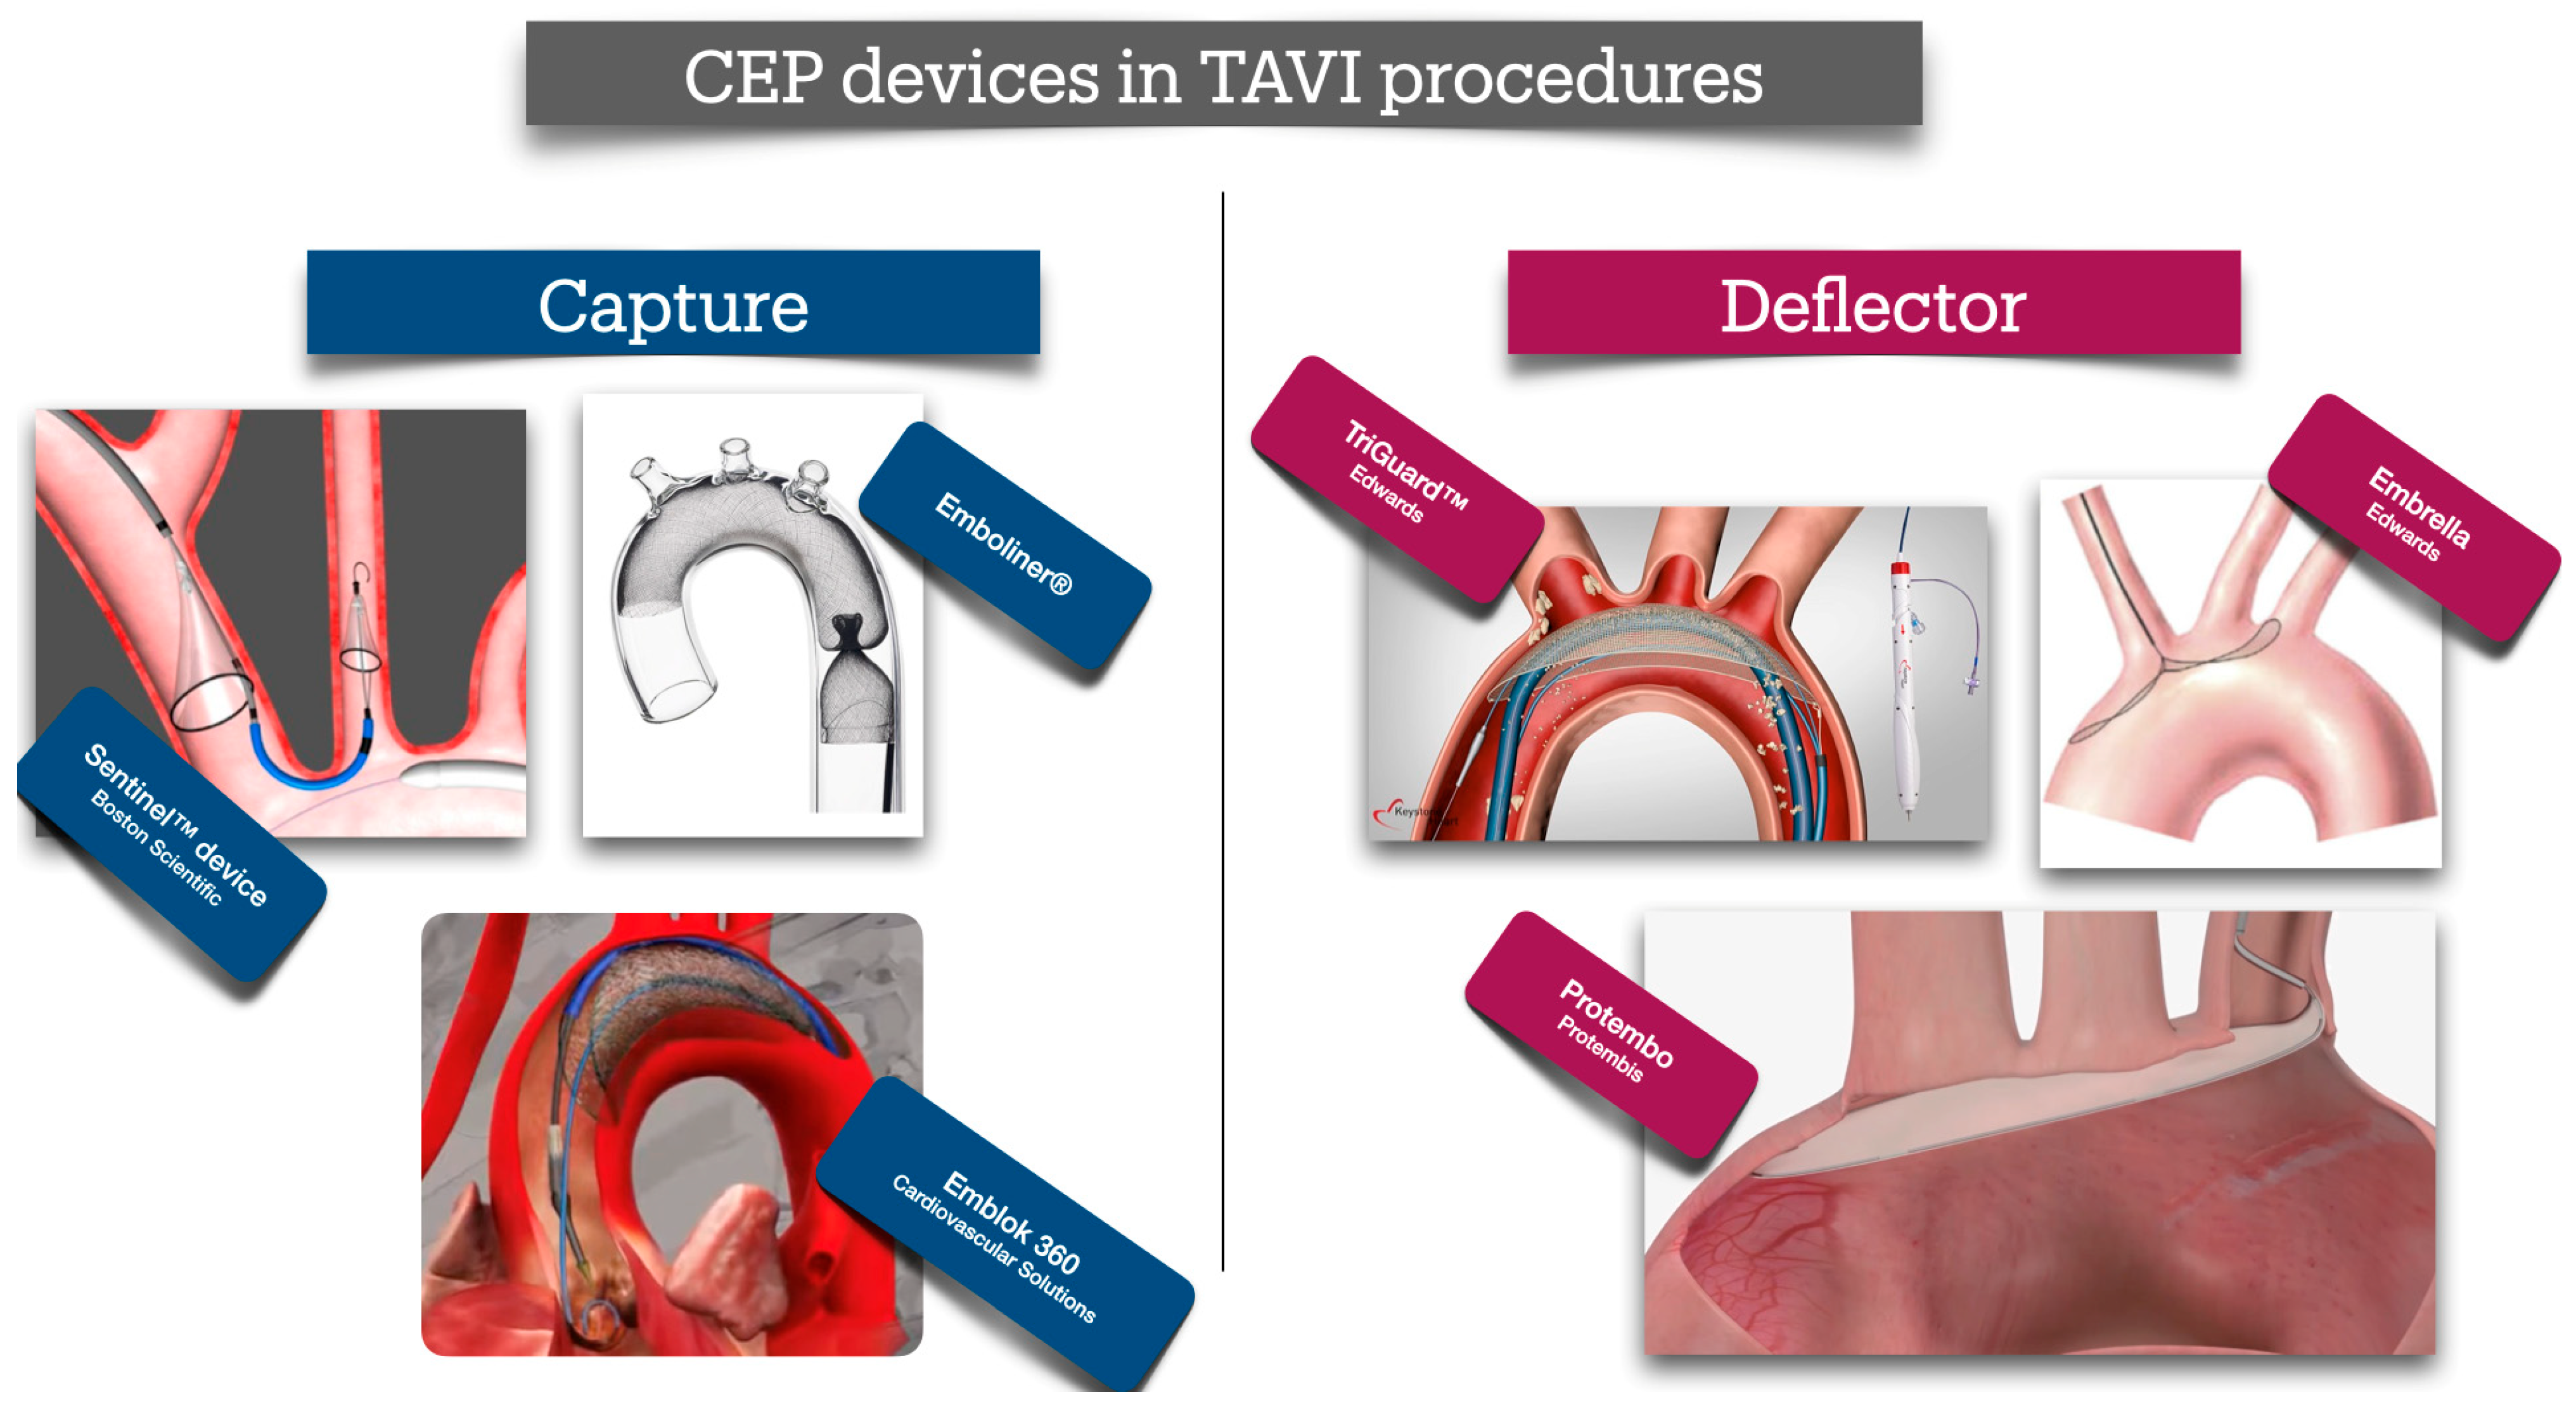

12. Devices to Reduce Periprocedural Stroke

| Device Name | Manufacturer | Type | Deployment Access | Cerebral Coverage | Key Characteristics |

|---|---|---|---|---|---|

| Sentinel CPS | Boston Scientific, St. Paul, MN, USA | Filter | Right radial artery (6 Fr sheath) | Brachiocephalic and left carotid arteries (partial; ~90% cerebral flow, excludes left vertebral artery) | Dual-filter system; captures debris; FDA-approved (2017); high technical success (94.5%); no significant stroke reduction in PROTECTED TAVR trial (RR 0.88, p = 0.566). |

| TriGuard 3 | Keystone Heart, Caesarea, Israel | Deflector | Femoral artery (9 Fr sheath) | All major cerebral arteries (innominate, left carotid, left subclavian) | Nitinol mesh (130-µm pores); deflects debris to descending aorta; improved cognitive outcomes in DEFLECT III; ongoing REFLECT trial (NCT02536196). |

| Embrella | Edwards Lifesciences, Irvine, CA, US | Deflector | Right radial artery (6 Fr sheath) | Brachiocephalic and left carotid arteries | Polyurethane membrane; deflects debris; higher lesion rates on MRI in some studies; not widely adopted. |

| Emboliner | Emboline, Inc., Santa Cruz, CA, USA | Filter | Femoral artery (9 Fr sheath) | Full cerebral (all supra-aortic branches) and non-cerebral vessels | Cylindrical nitinol mesh; captures 5× more debris (>150 µm) than Sentinel in SafePass 2; TAVR-focused, no CAS data; investigational. |

| ProtEmbo | Protembis GmbH, Aachen, Germany | Deflector | Left radial artery (6 Fr sheath) | All major cerebral arteries | Low-profile heparin-coated mesh; deflects debris; ongoing PROTEMBO C trial (NCT04205916); investigational. |

| Device | Study Design | Basic Results | Clinical Meaning |

|---|---|---|---|

| Sentinel CPS | Randomized controlled trial (n = 363 TAVI patients) | 94.5% technical success; reduced new cerebral lesion volume on MRI (p = 0.03); no significant stroke reduction at 30 days (5.6% vs. 9.1%, p = 0.25); debris captured in 99% of filters. | Reduced only the large strokes. Currently no indication for routine usage |

| TriGuard 3 | Randomized controlled trial (n = 258 TAVI patients) | 85.7% technical success; improved cognitive outcomes (p = 0.04); reduced total lesion volume on MRI (34% less, p = 0.057); no significant stroke reduction (8.3% vs. 11.4%, p = 0.48). | Unproven clinical benefit for stroke reduction. No indication for routine usage. |

| Embrella | Prospective pilot study (n = 52 TAVI patients) | 97.5% technical success; debris deflected in all cases; higher new lesion rates on MRI vs. controls (p = 0.02); no stroke reduction (10% vs. 11%, p = 0.89); limited adoption. | No randomized data. Decreased the size, yet increasing the number of lesions. Limit the new large lesions. No clinical benefit. No evidence for beneficial clinical use. |

| Emboliner | Prospective, non-randomized study (n = 24 TAVI patients) | 100% technical success; debris captured in 100% of cases (5× more particles >150 µm than Sentinel); no stroke rates reported; investigational, promising for full cerebral protection. | Easy to deploy, efficient to capture debris. No evidence for clinical application. |

| ProtEmbo | Prospective feasibility study (n = 30 TAVI patients) | 100% technical success; debris deflected in all cases; reduced lesion volume on MRI (p = 0.06); no stroke rates reported; ongoing PROTEMBO C trial | Successful deployment. Reduced lesion size. No clinical data on reducing clinically evident stroke complication |